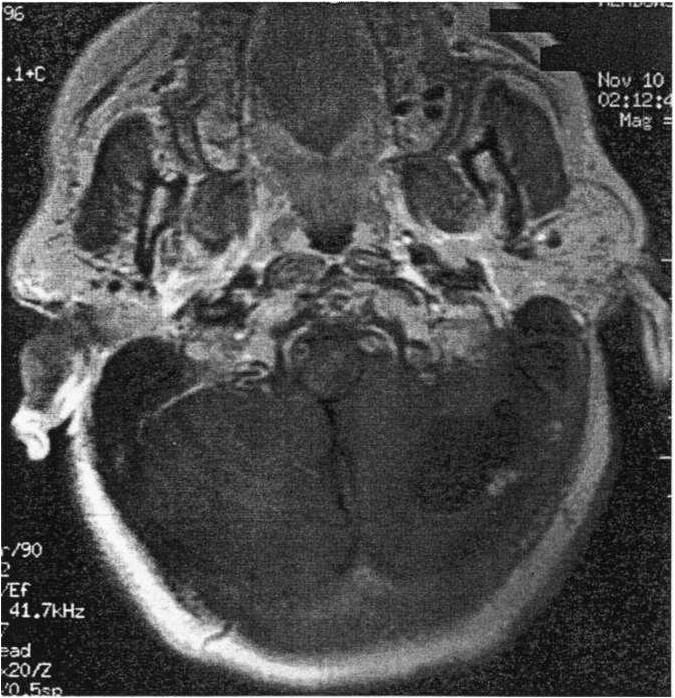

The natural history of DAVF is variable and includes spontaneous resolution, recruitment of meningeal arterial feeders, and the development of intracranial hypertension.

DAVF can present with pulsatile tinnitus, visual symptoms, papilledema, hydrocephalus, and intracranial hemorrhage.

The presence of retrograde cortical venous drainage indicates the potential for intracranial hemorrhage and mandates urgent treatment of the DAVF. Intracranial hemorrhage from a DAVF in the absence of retrograde cortical venous drainage has not been reported. Hemorrhage from a DAVF is associated with a high morbidity and mortality (approximately 30%). Ectatic dilation or venous occlusion of the involved sinus, multiple or dual ICA/ECA arterial feeders, or embolic stroke, in the absence of retrograde cortical venous drainage has not been reported to increase hemorrhage rates of DAVFs